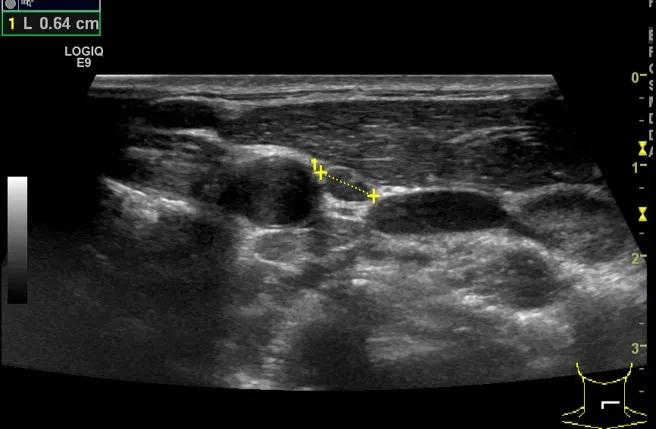

随后,徐栋教授进一步分享了五个临床实战病例,带来了更直观的热消融治疗经验。第一个病例是62岁肺癌患者,术后1年余发现双侧锁骨上淋巴结复发,侵犯神经,存在静脉回流、淋巴回流障碍,肿胀、疼痛非常明显。影像显示患者淋巴结边界不清、形态不规则,存在浸润,血流强化增强。由于患者在系统治疗后进展,且主要目的缓解症状、减瘤。局麻下行热消融术,从后向前逐层消融,热消融之后超声造影即刻评估显示完全充盈缺损,完全覆盖病灶。

(病例1图例)